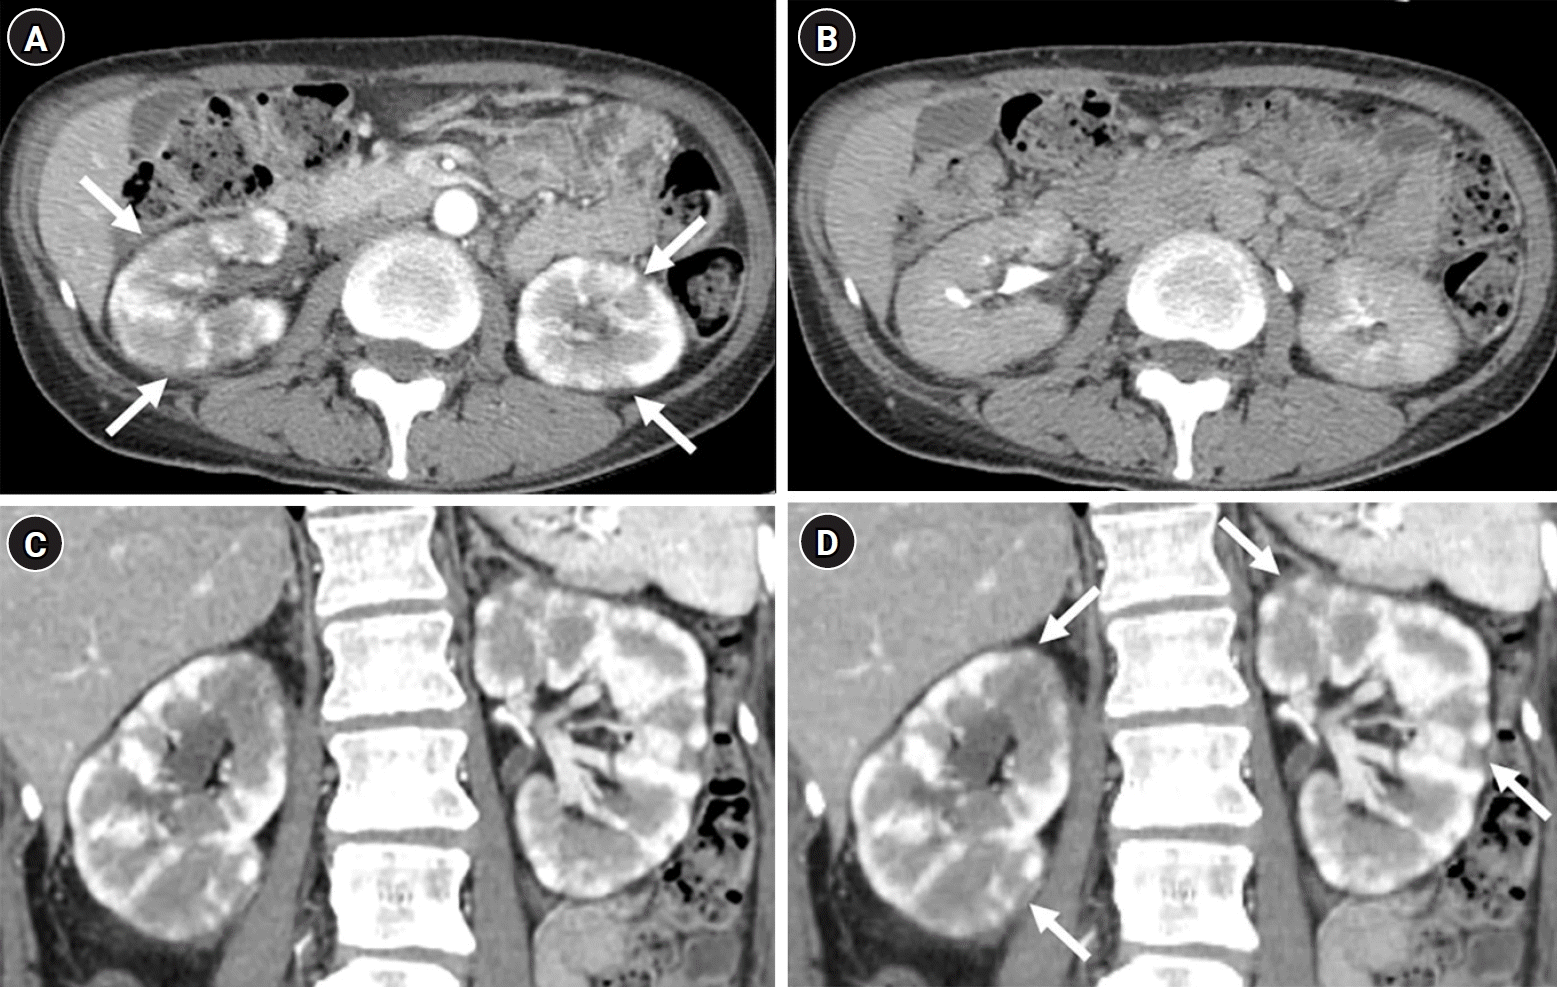

Fig. 4.

Ultrasound images of the right (A) and left (B) kidneys reveal diffuse enlargement of both kidneys, along with heterogeneous hyperechogenecity in the renal cortices.